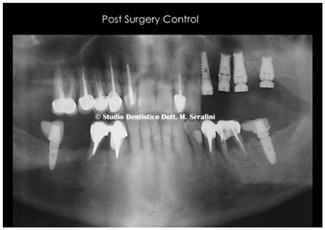

Figure 10: X-ray post Surgery control.

Figure 11: X-ray Control at 8 Months later.

Figure 12: (Post Surgery control) in this Photo you can see the in detail, the raised membrane “tent”.